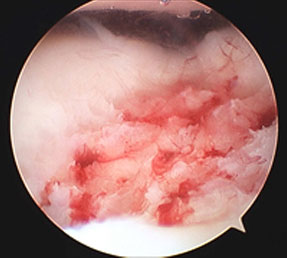

2.自家骨軟骨移植法(モザイクプラスティー)

膝関節の中でも後遺症を残しにくい部分(大腿骨滑車部)から、自分の正常な軟骨を骨ごと採取し、これを膝関節や肘関節の軟骨が損傷した部位に移植する方法です。

モザイクプラスティー前

モザイクプラスティー後